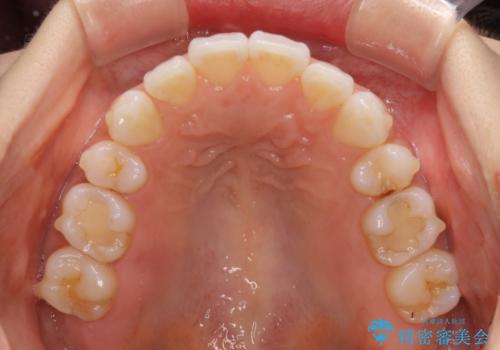

矯正治療の後戻り インビザラインによる再矯正治療

- 以前ワイヤー装置にて行った抜歯矯正の後戻りを気にして来院された患者様です。

前歯のデコボコにより、やや口元が突出した印象となっていたため、口元も引っ込めることとしました。

上下顎前歯に積極的にIPR(歯と歯の間を削る)を行い、インビザラインを用いて治療していくこととしました。

デコボコが解消されるのはもちろんのこと、突出感のあった前歯を引っ込めることができ、患者様には大変満足していただきました。